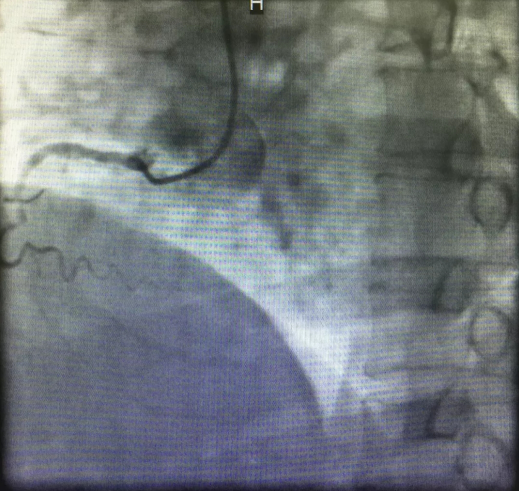

心内三完成啄木鸟 首例逆向开通冠脉CTO病变